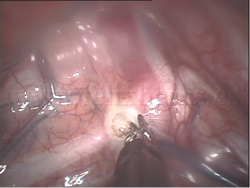

Simpatectomía torácica